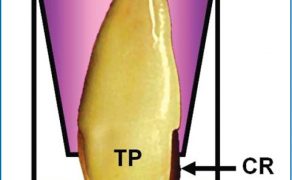

STRESZCZENIE: Skomplikowane złamania korony zasługują na szczególną uwagę ze względu na częstość ich występowania, wpływ na psychikę młodocianych pacjentów, różnorodność czynników przyczynowych i rozwiązań klinicznych. Głównym celem terapii po urazach zębów przednich jest rehabilitacja estetyczna i funkcjonalna. W pracy przedstawiono postępowanie po urazie siekaczy przyśrodkowych szczęki u 16-letniego pacjenta Poradni Stomatologii Dziecięcej Uniwersyteckiej Kliniki Stomatologicznej w Krakowie polegające na jednowizytowym leczeniu endodontycznym zęba 11 ze skomplikowanym złamaniem korony i natychmiastowej odbudowie estetycznej zębów 11 i 21. W pracy wykorzystano materiały biozgodne, takie jak uszczelniacz bioceramiczny i Geristore oraz kształtkę SeptoMatrix Cervical stworzoną do odbudowy ubytków klasy V. Udokumentowano również przebieg wizyt kontrolnych.

SUMMARY: Complicated crown fractures deserve special attention due to their frequency, impact on the psyche of adolescent [...]